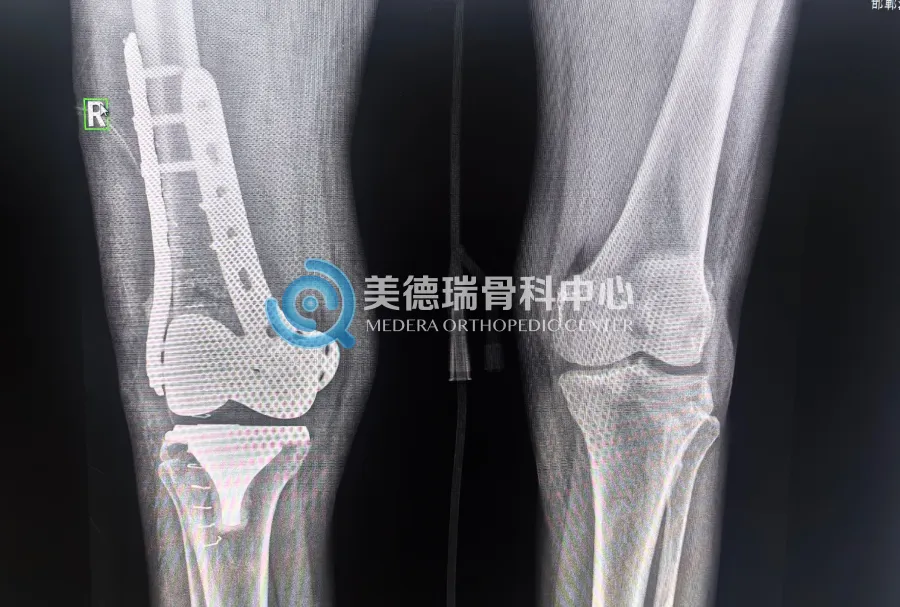

手术当天,石晶磊医生带领手术小组为患者实施手术。术中,专家团队发现,患者骨折远端骨量足以支撑双钢板内固定。团队果断选择双钢板的内固定术,既保证了骨折复位固定后的稳定性,又能减少手术创伤和手术时间,对高龄患者尤为重要。

手术顺利完成。专家团队叮嘱患者佩戴支具保护,并在骨折初步愈合后逐步开展膝关节功能训练,促进康复。